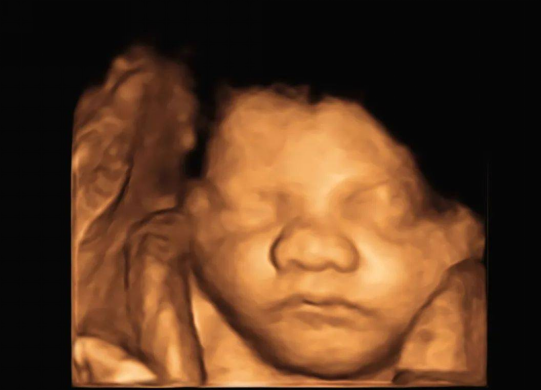

3. 产前超声精准筛查

开展早/中孕期胎儿出生缺陷筛查,配四维高端设备,结合规范流程,提升胎儿畸形检出率,护航母婴安全。